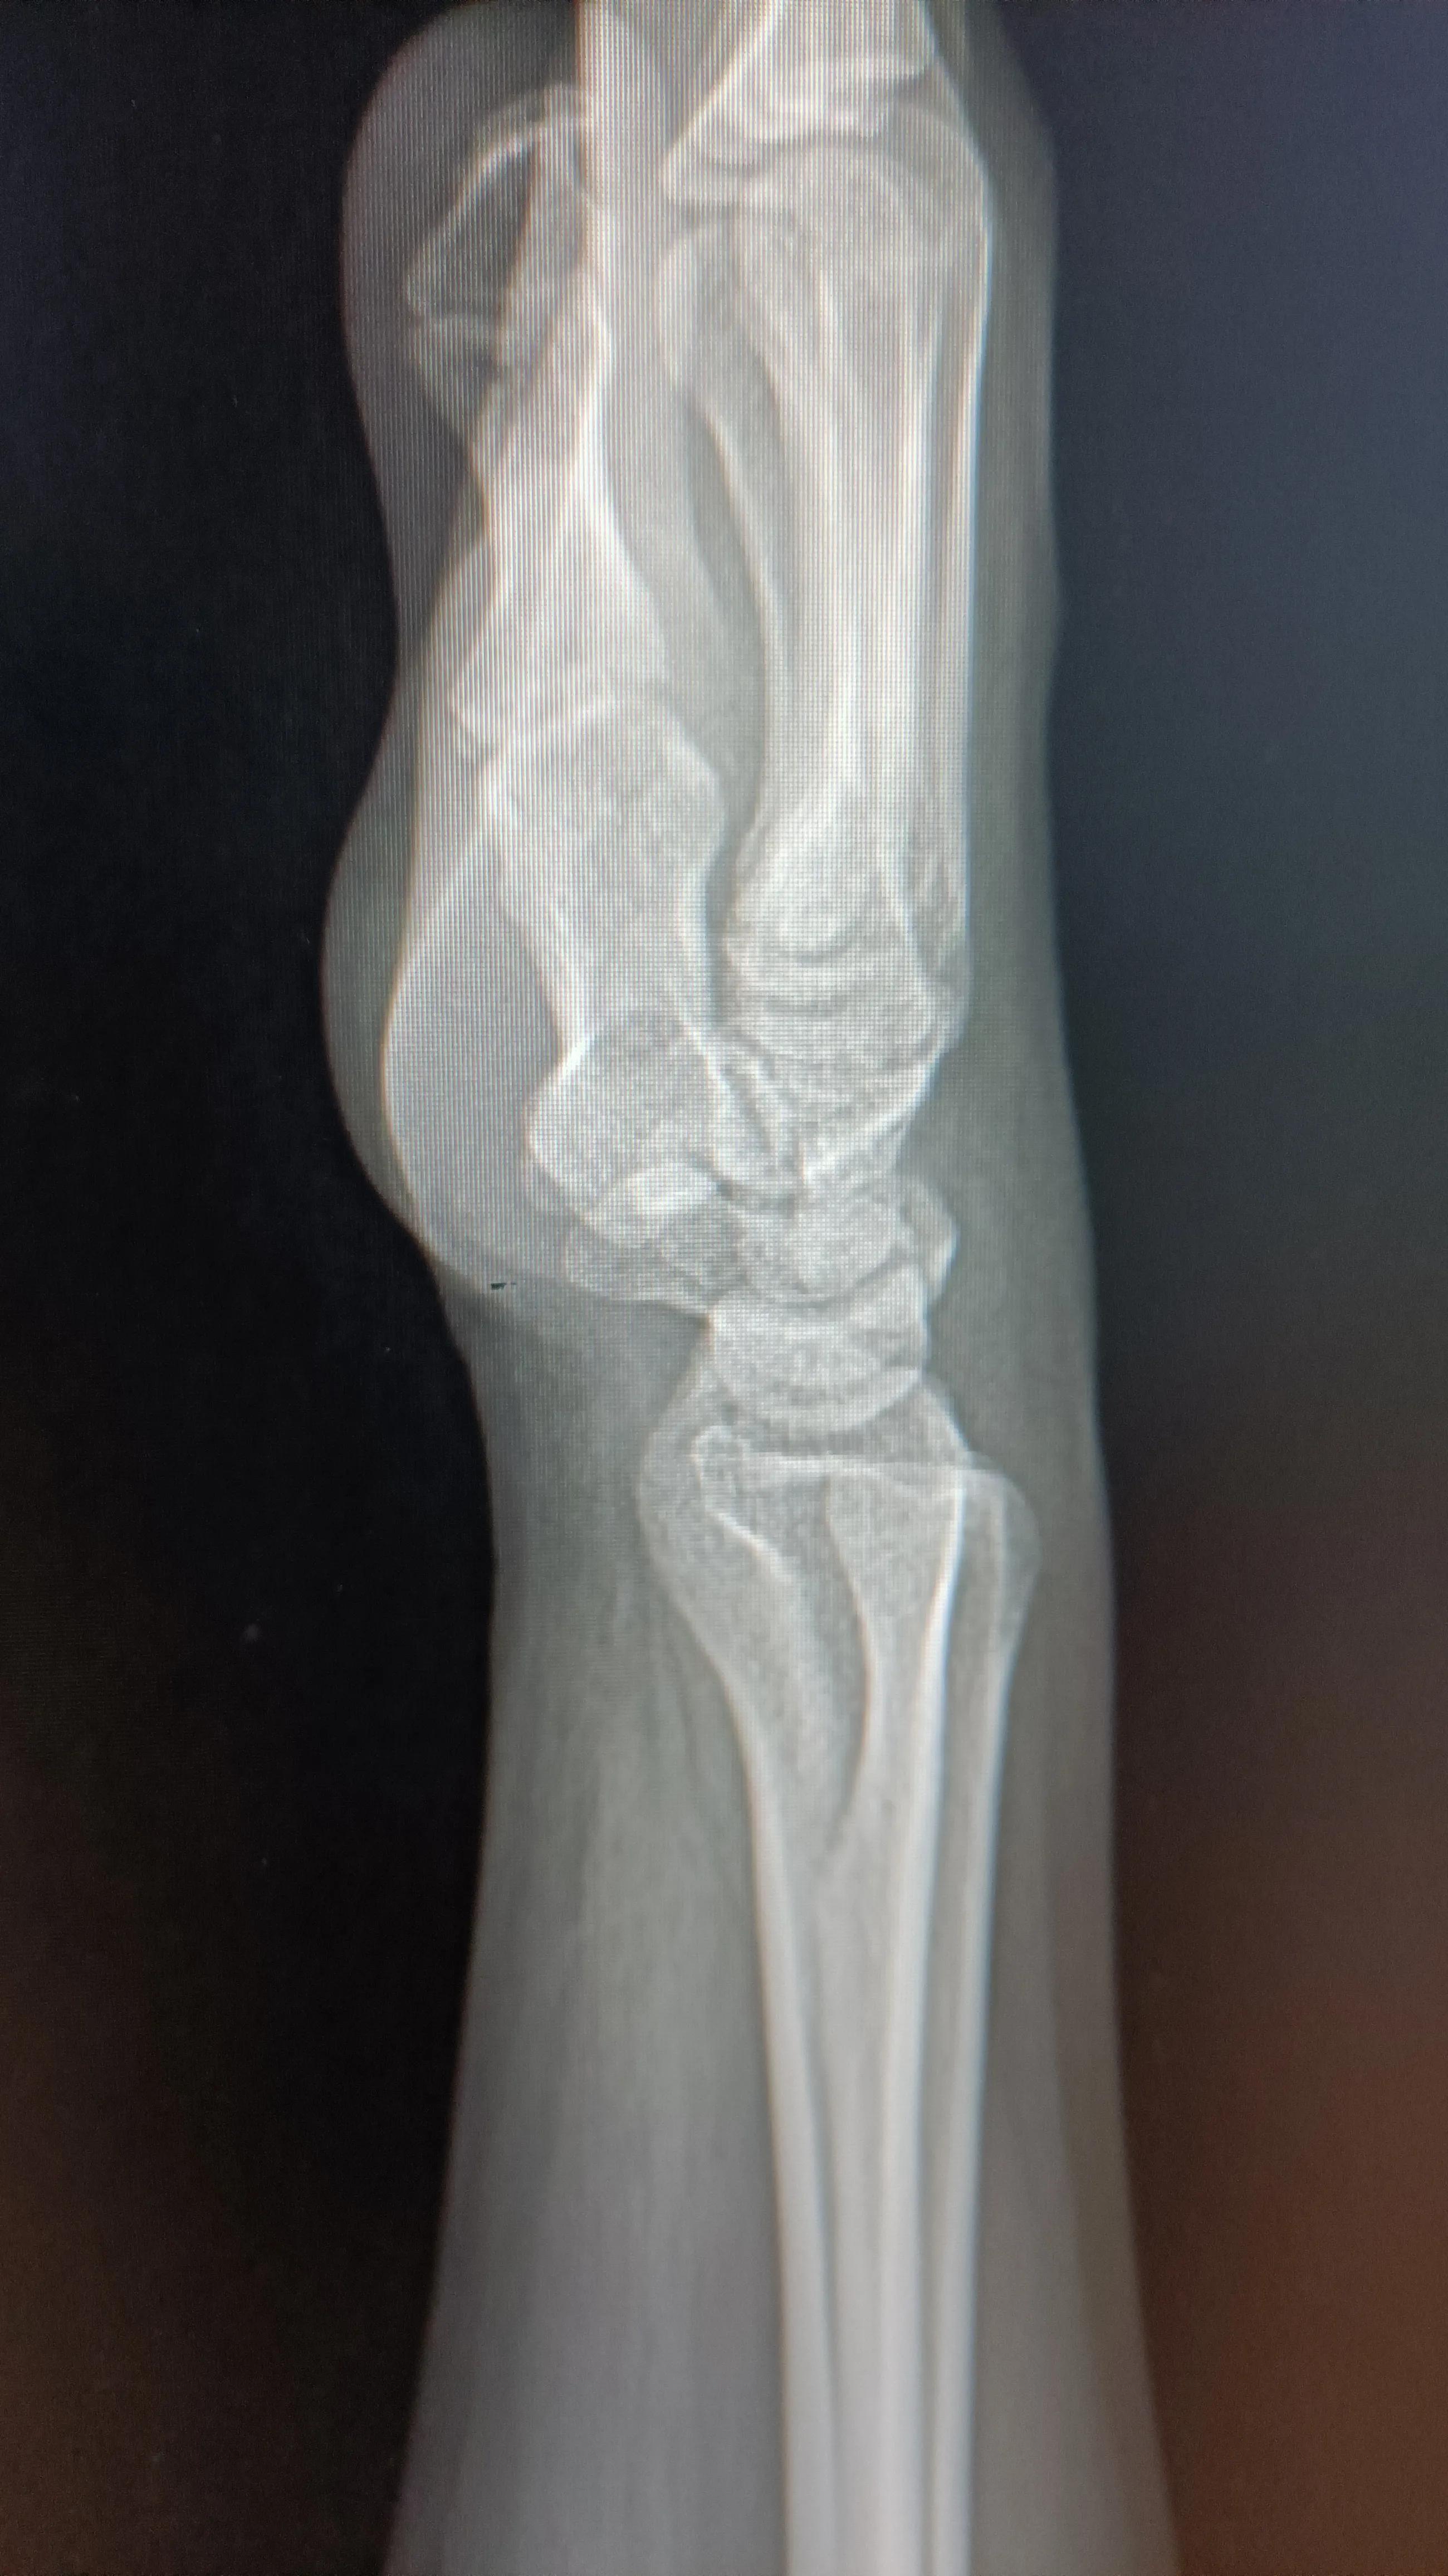

手足口继发的脱甲症一般出现在手足口病的恢复期,一般为手足口病后2-6周,指甲脱落时无痛无痒,没有炎症表现,一般先从甲根部、甲中部偏近端开始空甲,破坏,变白,然后慢慢与甲床分离,直至整个指甲分离脱落。愈合时间一般需要一个多月,新生甲板平整、光滑,无任何不适,预后良好!一般认为此病与手足口病严重程度无相关性,而与感染的病毒亚型有关。